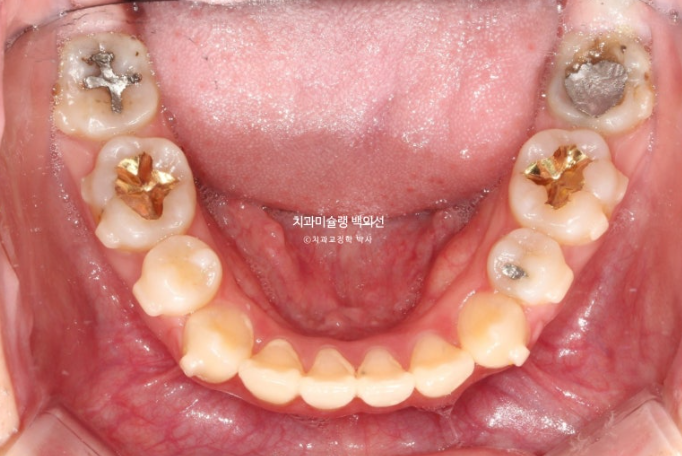

앞니는 가지런한 편이며 중심선도 거의 맞습니다.

교합은 좋은 상태이고

치열도 꽤 가지러한 편입니다.

거미스마일도 심한 편이었으며 돌출과 거미스마일 해소를 위해 작은어금니 4개를 발치하고 치료에 들어갔습니다.

치료방법은 인비절라인 선택하셨고 첫 세트 장치는 85개가 나왔습니다.

발치교정에서 거미스마일 개선을 위해서는 교정용 나사에 환자분이 뺏다꼈다 하는 고무줄 처방이 함께 들어갑니다.